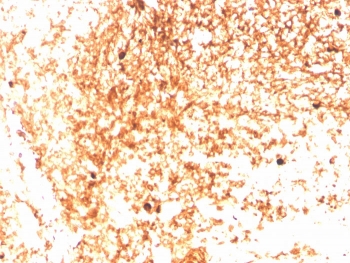

IHC staining of FFPE human tonsil with recombinant IgM antibody (clone IGHM/3803R). HIER: boil tissue sections in pH 9 10mM Tris with 1mM EDTA for 10-20 min and allow to cool before testing.